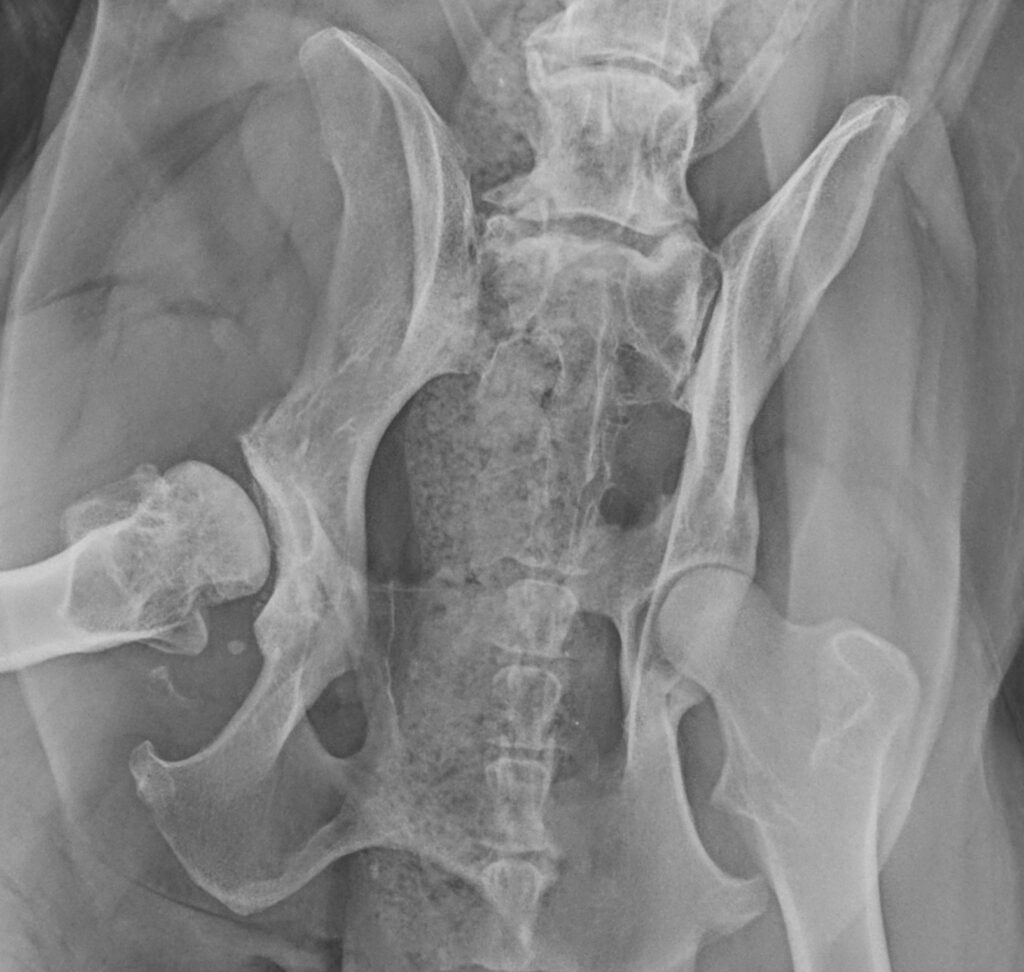

Understanding the hip joint

• Normal hip: a well-shaped femoral head (ball) sits snugly in the pelvis (socket), allowing smooth, even weight-bearing.

• Dysplastic hip: a shallow socket or deformed femoral head causes uneven loading, inflammation, and eventually arthritis.